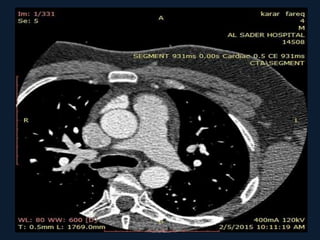

CTA done for this patient

CTA done forthis patient